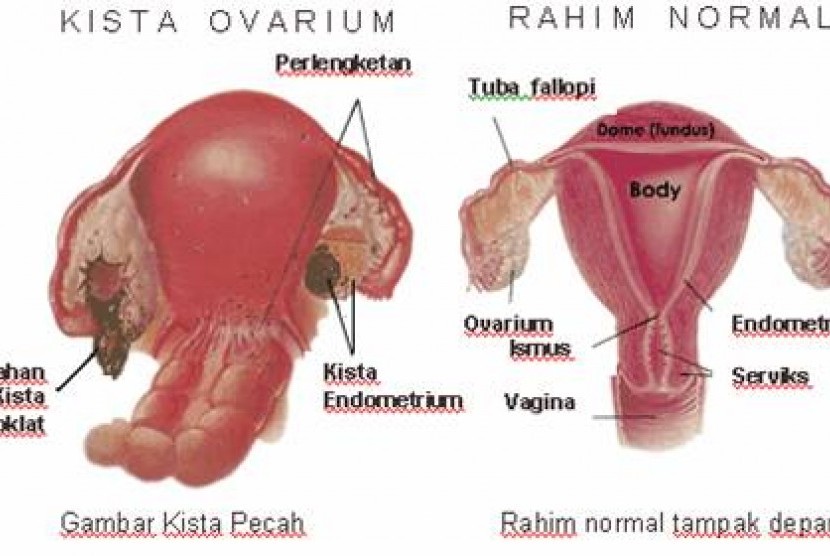

Agar Kista Tidak Berkembang Menjadi Besar | Republika Online

Agar Kista Tidak Berkembang Menjadi Besar | Republika Online

Bahaya kista: Bahaya Kista Ovarium

Bahaya kista: Bahaya Kista Ovarium